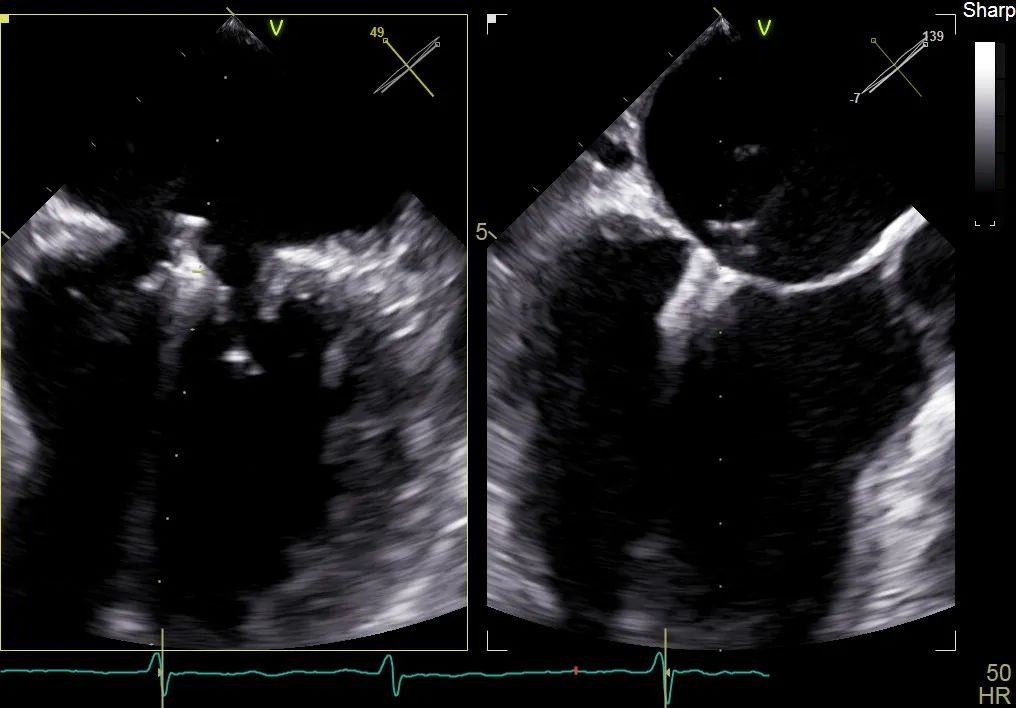

术前行经食道超声评估:继发性二尖瓣反流,反流程度4+;二尖瓣有效反流口面积(EROA) 0.81 cm²,缩流颈宽度18 mm,反流容积112.36ml,二尖瓣瓣口面积5.06 cm²,平均跨瓣压差5 mmHg,二尖瓣前叶(A2)长度15mm,二尖瓣后叶(P2)长度9 mm;左房内径54mm,左室收缩末期内径50mm,左室射血分数43%,肺动脉压83 mmHg。

术前食道超声可见二尖瓣重度反流,前后叶对合不全伴有间隙,且反流束宽度18mm